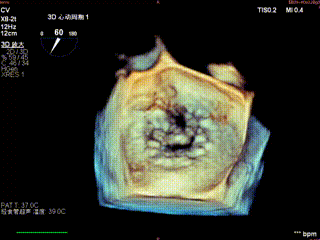

3D

怎么上穿刺鞘攻克巨大左房伴转位穿刺难关!温医大附一院周浩教授团队创新应用“导丝定位+可调弯鞘”技术完成高难度TEER手术_https://www.jmylbn.com_新闻资讯_第9张

3D带彩